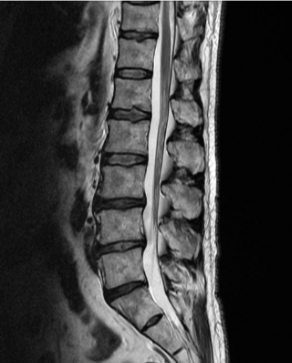

허리디스크를 정확하게 진단하기 위해서는 엑스레이로는 힘들며, MRI를 통해 검사해야 정확하게 볼 수 있습니다.

MRI가 몸에 좋지 않지만 허리 통증으로 엑스레이만 진행할 경우 오진이 많아 지속적인 통증이 계속된다면 허리디스크를 의심하고 MRI 검사를 한번 받아보시길 권유드립니다.